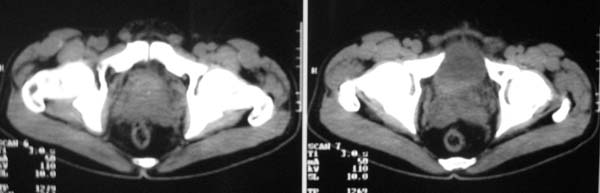

以下是引用zjzjr在2007-9-27 22:20:00的发言:[br]肠腔受推移,未见明显扩张及液平,所以考虑是肠外病灶, 间叶源性肿瘤?脂肪瘤?建议增强。

以下是引用guzhongliangddd在2007-9-27 23:21:00的发言:[br][br]与肠内高密度相同,病灶应该没有钙化,我认为首先考虑是间叶组织的良性肿瘤。建议楼主做后重建观察。中线区域大血管旁未见确切增大淋巴结。病灶对肠道只是推移关系。

以下是引用余辉在2007-9-27 22:24:00的发言:[br]暂考虑肠道间质来源肿瘤如小肠平滑肌肉瘤/瘤可能,应该增强